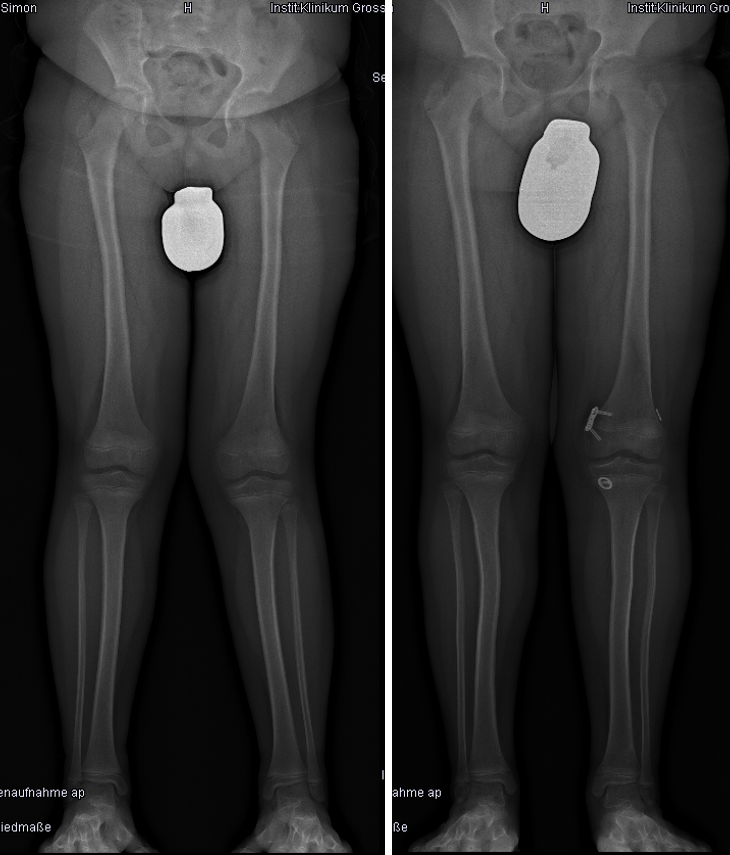

EOS low-dose Röntgenaufnahmen eines 16-jährigen Patienten welcher im Kriegsgebiet mit etwa 9 Jahren eine Schussverletzung am Kniegelenksnahen Oberschenkel erlitten hatte. Daraus resultierte eine ausgiebige Beinverkürzung mit Rotations- und Achsfehler des Beines. Aufgrund des „Abstehens“ des Beines konnte der Patient kaum Unterarmgehstützen benutzen.

Rechts ist eine Teilkorrektur mittels Taylor-Spatial-Frame abgebildet. Das aktuelle Restlängendefizit ist mittels Orthese ausgeglichen. Der Patient kann nun voll belasten und ist ohne weitere Hilfsmittel mobil. Als nächster Schritt folgt der operative Beinlängenausgleich mit einem Verlängerungsnagel.